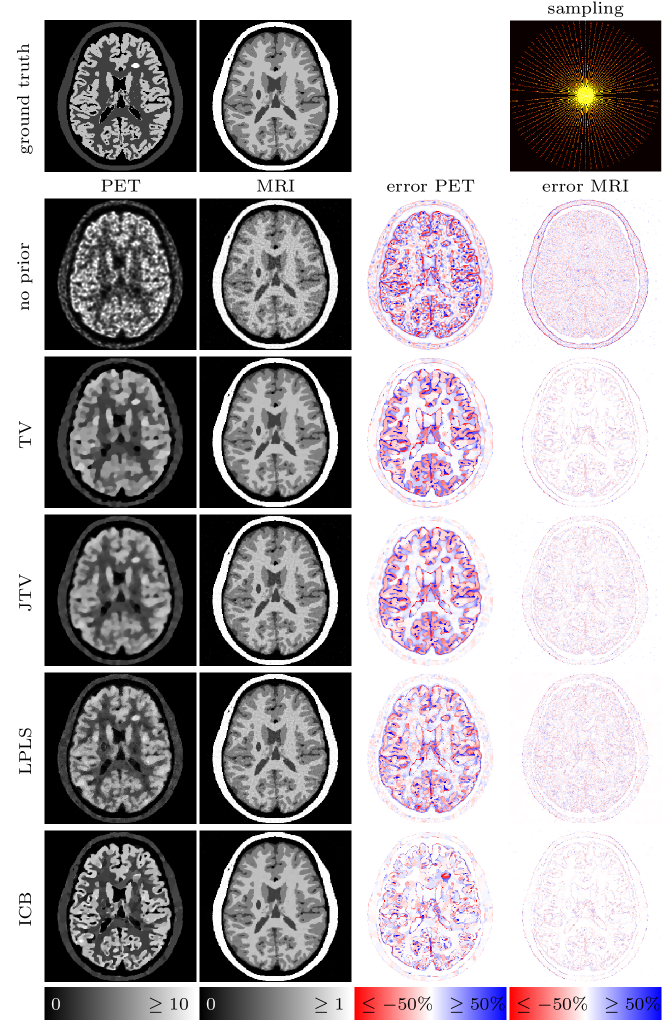

In case of MRI we use undersampled -space data, meaning that we sample the Fourier space only at a few frequencies specified by different geometries. For the sake of simplicity, the MRI operator hence consists of a 2-dimensional Fourier transform followed by a projection onto the geometric pattern of the corresponding sampling (cf. [20] . Note that we do not use a non-uniform Fourier transform since the chosen frequencies are still located on a Cartesian grid. However, the idea and method do not change for non-Cartesian methods. Eventually, Gaussian noise with an energy of approximately five percent of the total energy of the data set is added. We show four different types of undersampling in this work, which can be seen in Figure 6. The samplings introduce different types of artifacts and hence serve different purposes for the joint reconstruction setting which we elaborate on alongside with the results below.

![]() |

| (a) Full: | (b) Half: | (c) Spokes: | (d) Spiral: |

4.4 Results

Figures 9 to 12 show the results for four different MRI samplings and different types of regularization. The left two columns display the PET and MRI reconstructions, where all pictures are put onto the original scale of the ground truth, i.e. for PET and for MRI. If the reconstructions overestimate the image values beyond that scale, the corresponding pixels are set to the maximum value (note that an underestimation below zero is impossible due to the positivity constraint). The effective over- or underestimation of image values with respect to the ground truth can be assessed from the difference images on the right-hand side of the figures. Note that due to the missing weighting between gradients for JTV and LPLS, we had to rescale the PET data by a factor of in order to approximately provide the same range of image intensities for both PET and MRI. The results have then eventually been rescaled to their original range. We mention that due to the nonlinearity of the methods this may result in a slight change of quantitative values.

4.4.1 Full sampling

For a full sampling, already a separate reconstruction provides a visually perfect MR image, which remains the case for all priors. Here, the weighting for ICB is chosen such that the PET image does not influence the reconstruction of the MR image () and the procedure is similar to a PET reconstruction with an (evolving) anatomical prior. The MR reconstruction performed in parallel hence corresponds to a single channel BTV reconstruction. The quality of the PET image varies greatly. Without any prior, the PET image shows the typical noisy and blurry appearance of reconstructions from noisy Poisson data. The TV prior removes the noise, but highly oversmoothes the image. The first joint reconstruction method, JTV, is able to transfer some part of the sharp structures of the MR image to the PET image and increases its quality. However, the result remains too smooth. LPLS and ICB both show a substantial improvement of the image quality in terms of sharp edges and noise reduction. However, LPLS still features some remaining noise, and the lesion in the MRI not present in PET has been partly transferred. The result for ICB seems visually perfect on the shared structures of the image which can as well be assessed from the difference image. The only drawback is the smoothing of the hot lesion only present in the PET image, while we however observe that the MRI lesion has not been transferred. The observations are as well confirmed by the SSIM values in Table 1.

4.4.3 Spokes sampling

The situation for a spokes sampling is almost identical to a full MR sampling. Since already a TV prior removes the resulting grain artifacts, we again choose the weighting for ICB such that the PET image does not influence the MR image (). Interestingly, JTV and LPLS decrease the quality of the MR image, both visually and in terms of SSIM, by re-introducing some part of the noise. However, the PET image still benefits significantly from the influence of the MRI. ICB again shows the best performance for PET, sharpening the edges and restoring the quantitative values, where we again observe the attenuation of the hot lesion and transfer of the MR lesion.